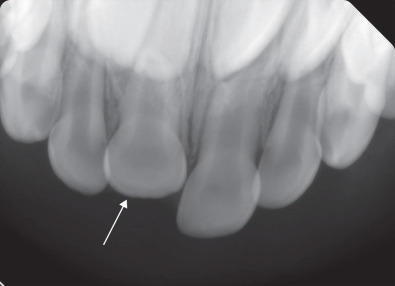

The periodontal ligament (PDL, Fig. 1.18.3 ) is a set of connective tissue fibers that secure the tooth to the adjacent alveolar bone. It provides for physiologic mobility and helps support the tooth against compressive forces through its insertion into cementum (via Sharpey’s fibers). It is seen on dental radiographs and orthopantomograms as the radiolucent line between the tooth and the cortical margin of the adjacent alveolar bone known as the lamina dura (see Fig. 1.18.8 ). The PDL is highly vascular, providing blood supply to the adjacent cementum. Osteoblasts and cementoblasts are within the PDL, allowing for reparation of alveolar bone and cementum. The viability of the PDL and associated cells after trauma is important in the prognosis of the injured tooth. Loss of the PDL leads to ankylosis of the tooth to the bone or external resorption of the tooth.

Intraoral radiographs: Intraoral radiographs are high-resolution two-dimensional radiographs that include bitewings, periapical, and occlusal film used by dentists and dental specialists. Bitewings evaluate tooth crowns and alveolar bone to detect caries and periodontal disease. They have little utility in the setting of trauma. Periapical radiographs (PA) show the crowns and roots of 1–4 teeth. They show the periodontal ligament, and alveolar bone around the tooth. Multiple angles may be needed to detect a root fracture. PA films can be used to confirm reduction following splinting of avulsed and luxated teeth by comparing the position of the tooth root to the surrounding cortical margin of the socket (lamina dura). Occlusal films are taken perpendicular to the occlusal plane of the maxilla and mandible and are larger than PAs ( Fig. 1.18.8 ). They are easier to obtain than periapical radiographs in the trauma setting as they do not require that the film or sensor be placed into the lingual or palatal tissue. They can be used to identify crown/root fractures, luxation injuries, and are useful in detection of radiopaque foreign bodies or tooth fragments in the surrounding soft tissue (e.g. floor of mouth, lips, vestibule).